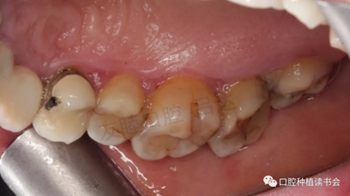

圖6 左側(cè)上頜后牙區(qū)

圖7 右側(cè)上頜后牙區(qū)

圖8 下頜前牙區(qū)

圖10 46種植體頰側(cè)中央粘膜邊緣膿腫,形成瘺管。